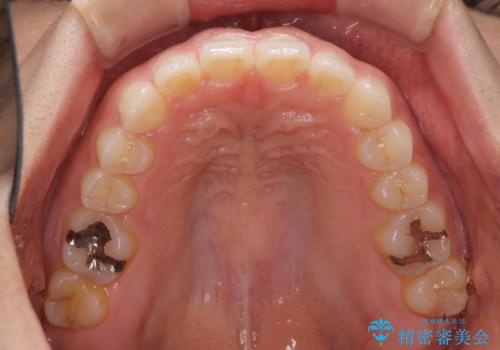

隙間の空いた前歯を閉じたい インビザライン矯正

- 前歯の隙間を気にして来院された患者様です。

隙間、捻転ともに軽微でありましたが、下顎前歯の突き上げにより隙間ができていたため、インビザラインを用いて咬み合わせを改善しながら前歯の歯列を整えていくこととしました。

当初は1年程度で終えられると思いましたが、治療途中から装着時間が短くなったり、来院間隔が長期になったりとし、結果として4年半以上の治療期間となりました。

治療途中に上顎前歯は失活してしまいましたが、変色が顕著ではないため、経過を見ていくこととなりました。